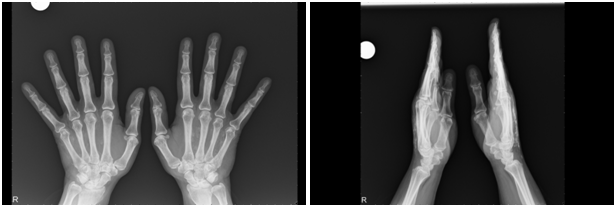

The radiological studies of both hands (Figure 1) revealed clumps of calcification of the soft tissues suggesting a connective tissue disoerder. The calcification extended to involve the subcutanous tissue which can be seen on the lteral view. A periosteal reaction as a part of the infammatory process also can be seen at the medial border of the 5th metacarpal bone. Xray of both feet did not reflect any bony changes. Only a mild hallux valgus deformity.

Figure 1 X-ray of both hands of 51 years old woman showing calcification of the soft tissues 5 years after injection of collagen into the web spaces.